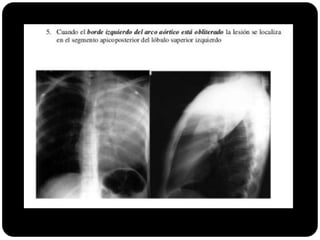

E agora?

 Se borrar arco aórtico qual o segmento

afetado?

 Apico posterior (LSE)

 Se borrar aorta ascendente qual o segmento

 Anterior (LSD) ou segmento medial (LM)